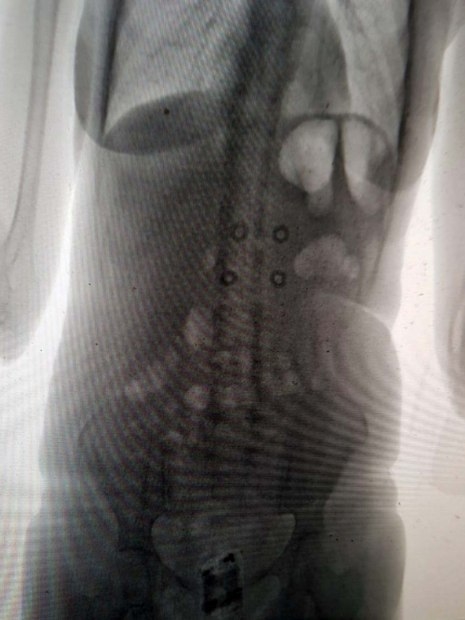

Agentes da Secretaria estadual de Administração Penitenciária (Seap)

flagraram uma mulher com um celular escondido no ânus, quando ela

tentava entrar no Presídio Evaristo de Moraes, em São Cristóvão, no Rio

de Janeiro.

Andréa Pereira dos Santos, de 38 anos, passava pelo

scanner corporal da cadeia da Zona Norte do Rio, quando os inspetores

penitenciários descobriram o celular

em suas partes íntimas.